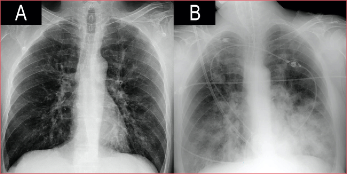

Varón de 53 años, con diabetes tipo 2 en tratamiento con insulina y mal controlada (HbA1c 11%). Acudió al Departamento de Urgencia por un cuadro catarral de cuatro días de evolución. A su llegada tenía insuficiencia respiratoria e hipotensión, la radiografía no mostraba infiltrados parenquimatosos (Figura 1). La reacción en cadena de la polimerasa fue positiva para el virus influenza A (subtipo H1N1 variante 2009), por lo que se inició el tratamiento con oseltamivir junto con ceftriaxona y levofloxacina. El antígeno urinario para Streptococcus pneumoniae y Legionella pneumophila tipo 1 fue negativo. Tras 24 h, el estado clínico empeoró y se decidió el ingreso en la Unidad de Cuidados Intensivos. Los análisis de laboratorio revelaron leucocitosis y marcadores inflamatorios elevados. A pesar del soporte respiratorio con oxigenoterapia de alto flujo, el paciente no mejoró y requirió intubación orotraqueal y ventilación mecánica invasiva. En la radiografía posintubación, apareció una condensación incipiente en el lóbulo inferior izquierdo, por lo que se sustituyó ceftriaxona por meropenem. Las siguientes 48 h estuvieron marcadas por un empeoramiento progresivo: insuficiencia respiratoria a pesar de la ventilación protectora, shock con pobre respuesta a fármacos vasoactivos e inotrópicos, coagulopatía e insuficiencia renal aguda, con anuria. Se inició hemodiafiltración venovenosa continua. A las 72 h del ingreso en la Unidad de Cuidados Intensivos, continuó la progresión clínico-radiológica con evidencia de infiltrados bilaterales algodonosos (Figura 1) y aumento de la necesidad de FiO2.

Figura 1. Evolución radiográfica en las primeras 72 horas.

Es importante destacar que, dentro de las alteraciones en los estudios por imágenes, se aceptan no solo los hallazgos típicos en la TC (signo del halo o nódulos pulmonares múltiples rodeados de áreas de vidrio deslustrado),11 sino también las alteraciones visibles en la radiografía portátil. Con esto se pretende incluir dentro del algoritmo a pacientes inestables que no puedan ser trasladados a la sala de radiodiagnóstico, como ocurrió en nuestro caso, donde la rápida progresión radiológica paralela a la mala evolución clínica fueron criterios suficientes para iniciar la terapia antimicótica sin necesidad de una TC.